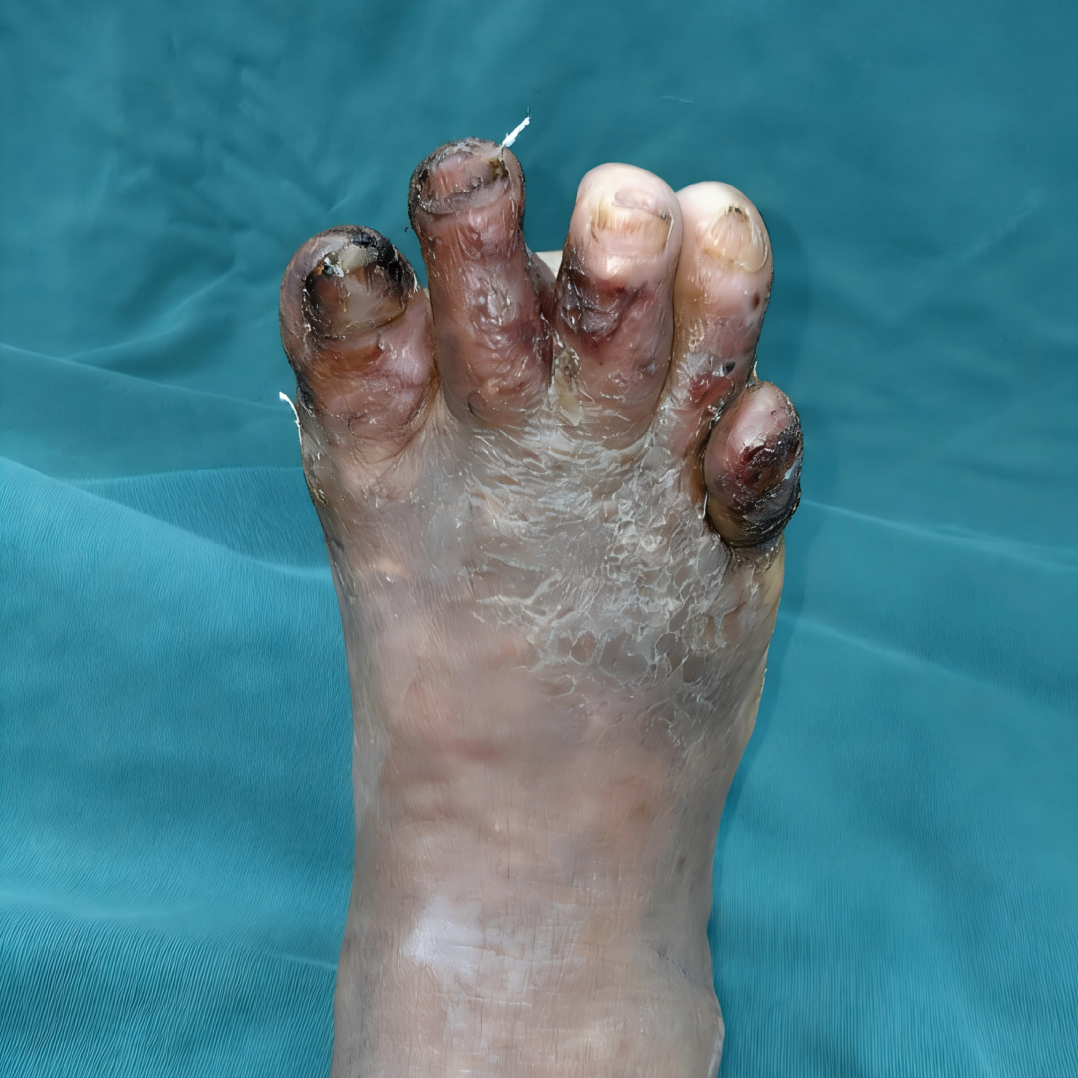

患者荣先生三个月前因抓破右足底,未行正规处理致创面溃烂扩大、加深,伴渗液与间歇性疼痛,且病情发展迅速,情况复杂棘手。经详细检查,患者足底及第1-5足趾出现感染、脱位、骨折,并伴有明显积液和积脓。

术前